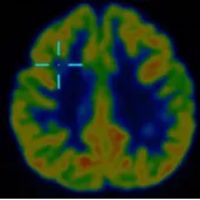

借助医院先进的高清晰度、高对比度薄层扫描核磁共振,配合PET-CT检查,终于在右额叶发现了一个极其微小的致痫病灶。这个位置,与脑电图提示、以及临床发作特征完美吻合。更幸运的是,虽然病灶位置深,但范围很小。

这一发现,为精准治疗打开了大门。